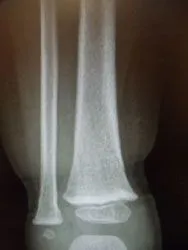

The two pics below are of a nondisplaced subtle toddler tibia fracture. There is a spiral oblique fracture of the distal tibia

Xrays of nondisplaced toddler fracture